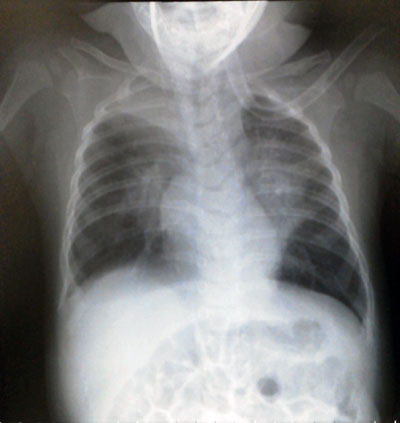

昨日撮ったX線写真。

炎症の白い影が減っている。

そして入院後に再度撮影した画像を見せて頂いた。

肺の上部が潰れている。 (←ロールオーバー有り)

かなり良くない状態であった。

つまり入院時はまだピークではなかったってこと。

ケッコー危ない状態だったんだな・・・。